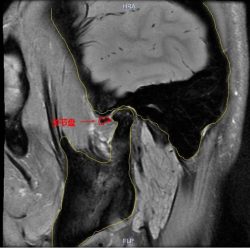

磁共振高清成像(≤2mm):对软组织分辨率高,可直观观察关节盘的位置、形态及运动情况,判断是否存在关节盘移位、穿孔或关节腔积液等。

(关节盘不可复性前移位的磁共振图片)